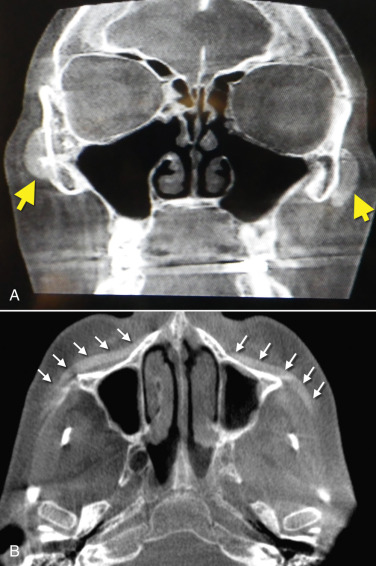

Although silicone implants are radiolucent, they can be visible by enhancing some CT scans and the titanium screws are always visible ( Fig. 7.34 ).

The self-drilling screw allows easy seating of the screw without the need for a drill. The two best regions to place a fixation screw are in the thick bone of the lateral piriform aperture or the thick buttress bone in the lateral maxilla ( Fig. 7.26 ). Occasionally, a screw may be placed through the maxilla and perforate the maxillary sinus. Although I try to avoid placing screws in the sinus, it is a common procedure in orbital trauma, maxillary osteotomy, and sinus surgery. Screws in the sinus are not in themselves problematic, but could possible increase the possibility of sinus infection. Finally, the thin bone of the anterior maxillary sinus is less dense to retain a screw. Fig. 7.27 shows typical screw fixation of implants.

Some patients have extremely thin “potato chip” bone on the maxillary sinus and this can be easily perforated or fractured during routine dissection ( Fig. 7.54 ). This is most often seen with novice surgeons but can occur with any surgeon. If a moderate perforation occurs during implant dissection, the procedure can continue and the implant can lay over the perforation. The surgeon must take care not to allow debris to fall into the sinus through the perforation. Since patients are already on antibiotics from the implant procedure, no other coverage is necessary unless the patient becomes symptomatic with sinus-related problems. An antral perforation may result in bleeding from the nose as blood that entered the sinus may drain, but this is not active hemorrhage and is self-limiting.